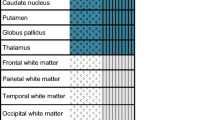

MRI acquisition was routinely performed with 3 T Siemens MR Scanners (Magnetom Vida, Magnetom Verio or Magnetom Skyra fit; Erlangen/Germany). Certified staff neuro-radiologists from the Department of Neuroradiology of the Inselspital, University Hospital Bern quantified MRI findings as part of their clinical routine. The MRI report based on four different patterns known as MR-lesion patterns (MLP), originally described by Barth et al. [13]. According to this publication, MRI findings were classified based on the DWI and apparent diffusion coefficient ADC restrictions. An axial T2w and a coronal T2w-FLAIR (Fluid-Attenuated Inversion Recovery) were used to detect old hyperintense abnormal signal alterations, to exclude chronic infarction, or as a reference to exclude T2- “shine through” effect. ADC values were measured in pre-defined regions of interest located in the cerebral cortex, the cerebellar cortex, the hippocampi, the basal ganglia, both thalami and the brain stem. The cerebral cortex contained eight regions of interest’s (one in each frontal, parietal, temporal, and occipital lobe). Region of interest sizes were 4 mm2 for the cerebral and cerebellar cortex and the hippocampi, 10 mm2 for the basal ganglia, thalami and the brain stem. Regions of interests that revealed restricted diffusion and corresponding decreased ADC values < 650 × 10–6 mm2 were considered as pathologically restricted as previously suggested [16]. Barth and colleagues then defined four different patterns called MR-lesion patterns (MLPs) based on DWI/ADC restriction in the different regions of interest. MLP 1 was defined as an absence of any gray matter lesion; MLP 2 as purely cortical grey matter lesions; MLP 3 as the presence of basal ganglia lesions without involvement of other subcortical grey matter (with or without cortical lesions); and MLP 4 as lesions of the thalami and/or hippocampi and/or brain stem (with or without cortical or basal ganglia lesion). Representative examples are displayed in Fig. 1.